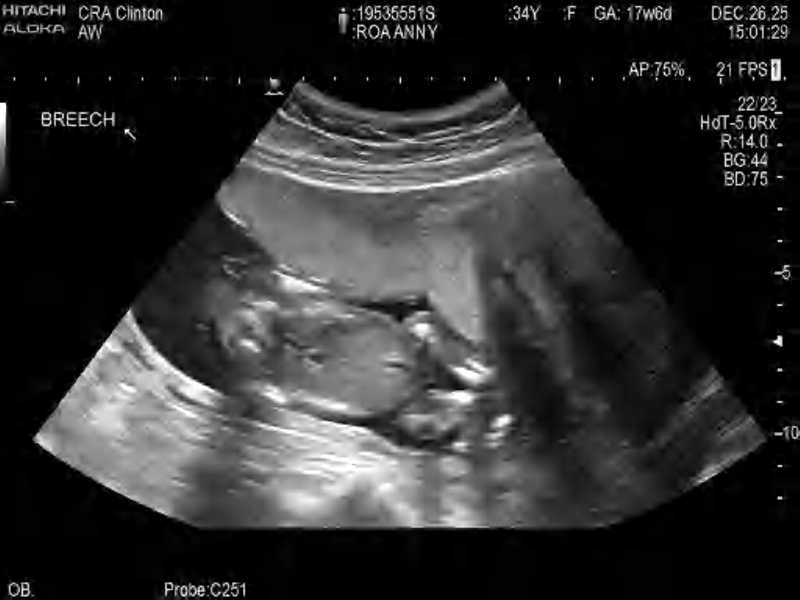

Photo 2025